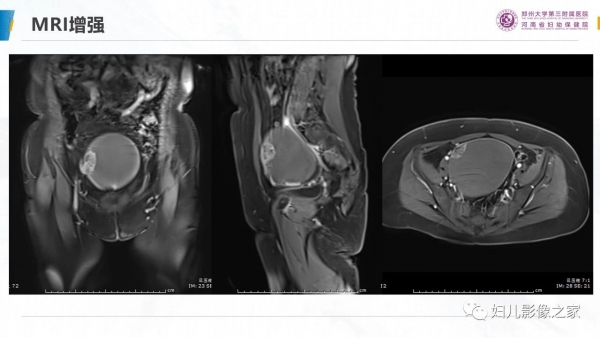

卵巢透明细胞癌

病史:患者女,57岁

主诉:尿频2月余,发现盆腔囊肿4天

现病史:2月前出现尿频尿急,4天前于当地医院彩超发现盆腔囊肿,无女性生殖器官出血,无腹痛

专科检查:于耻骨联合上方可触及拳头大小肿物